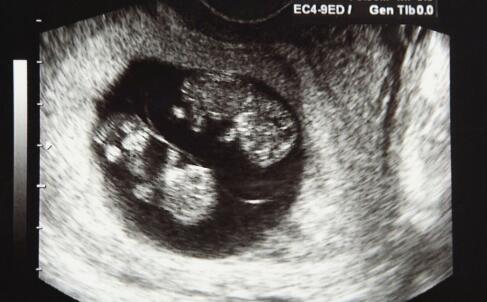

但是女人在怀孕时,阴道酸碱度会失衡,免疫力下降,很简单呈现阴道炎,而孕育胎儿的子宫又经过宫颈管与阴道相通,假如人流手术前不进行必要的查看医治,就或许把致病菌直接带入宫腔,导致发生各种炎症。比方子宫内膜炎等,患者或许呈现高热、腹痛,严峻的也或许危及生命。